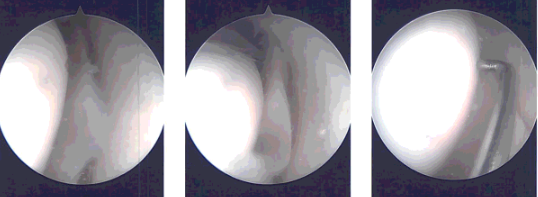

Time-out was called. Preoperative antibiotic was given. A lateral incision was given for the entry portal. Scope was entered. Patellofemoral compartment showed grade 1 to grade 2 osteoarthritic changes.

A medical entry portal was made using a spinal needle. Examination of the medial compartment showed a complex tear of the posterior horn of the medial meniscus. The tear was debrided. Medial meniscus was debrided with the use of straight biter, upbiter, and shaver.

Examination of the intercondylar notch showed intact ACL with degeneration. Examination of the lateral compartment showed medial frayed margins of the lateral meniscus which was debrided with the use of upbiter as well as the shaver.

Intraoperative images